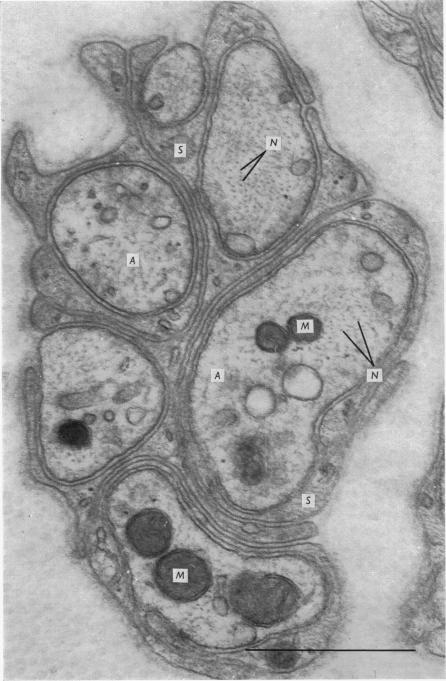

1. Podophyllotoxin, colchicine and griseofulvin inhibit the intra-axonal movement of noradrenaline storage vesicles in cat hypogastric nerve/inferior mesenteric ganglion preparations maintained in vitro, cause the disappearance of axonal microtubules and inhibit the assembly of microtubules from tubulin in vitro. The order of potency of the three effects is podophyllotoxin greater than colchicine greater than griseofulvin. 2. Lumicolchicine is without effect on the three parameters and does not interfere with the binding of tritiated colchicine to tubulin. 3. Podophyllotoxin causes a more rapid loss of microtubules from axons than the same concentration of colchicine. 4. The experiments provide strong evidence that microtubules are components of the system responsible for the intra-axonal migration of noradrenaline storage vesicles.

1. 鬼臼毒素、秋水仙碱和灰黄霉素可抑制体外培养的猫腹下神经/肠系膜下神经节标本中去甲肾上腺素储存囊泡的轴突内移动,导致轴突微管消失,并在体外抑制微管蛋白组装成微管。这三种作用的效力顺序为:鬼臼毒素>秋水仙碱>灰黄霉素。2. 光秋水仙碱对这三个参数无影响,且不干扰氚标记秋水仙碱与微管蛋白的结合。3. 与相同浓度的秋水仙碱相比,鬼臼毒素使轴突微管丧失的速度更快。4. 这些实验提供了有力证据,表明微管是负责去甲肾上腺素储存囊泡轴突内迁移的系统的组成部分。